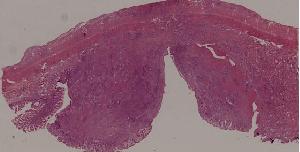

92.肠伤寒